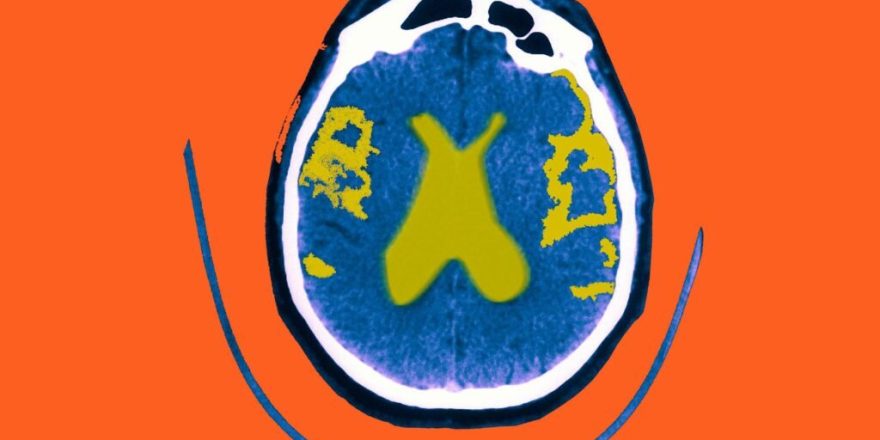

چاقی و تخریب اعصاب مغز

محققان ربط بین چاقی و اختلالات عصبی همانند بیماری آلزایمر را کشف کردند. پژوهش تازه مشخص می کند که رژیم غذایی با قند بالا – که نشانه چاقی است – علتمقاومت به انسولین در مغز می‌بشود. این مقاومت به‌نوبه‌خود خطر تخریب عصبی یا دژنراسیون مغزی را افزایش می‌دهد.

بر پایه مقاله منتشرشده در PLOS Biology، ارتباطی بین چاقی و اختلالات عصبی همانند بیماری آلزایمر وجود دارد. در این تحقیق از مگس میوه معمولی منفعت گیری شد و نشان داد که رژیم غذایی با قند بالا علتمقاومت به انسولین در مغز می‌بشود. طی این مقاومت، توانایی حذف باقی مانده عصبی در مغز افت می‌یابد و درنتیجه خطر تخریب عصبی افزایش اشکار می‌کند. این تحقیق می‌تواند به تشکیل درمان‌هایی برای افت خطر ابتلا به بیماری‌های عصبی پشتیبانی کند.